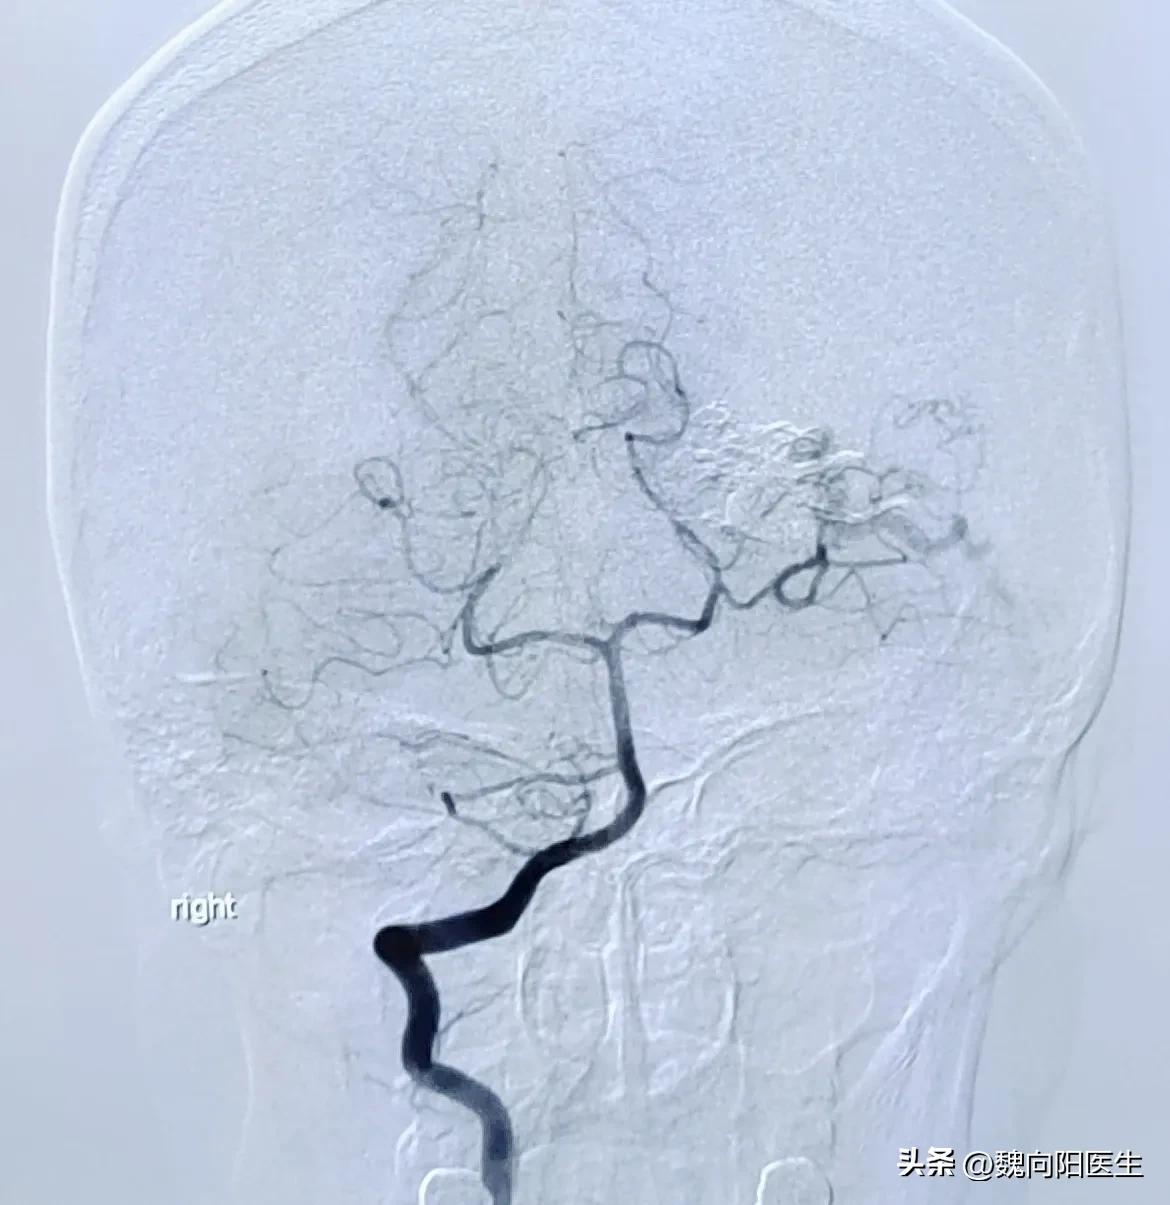

当时考虑出血部位不典型,且并没有外伤史,考虑患者是否存在血管畸形,立即行脑血管造影检查。

当脑血管造影做完之后,发现是左侧枕叶血管畸形。经与患者家属充分沟通之后,决定采取介入手术治疗,立即给患者行经导管动静脉畸形栓塞术。